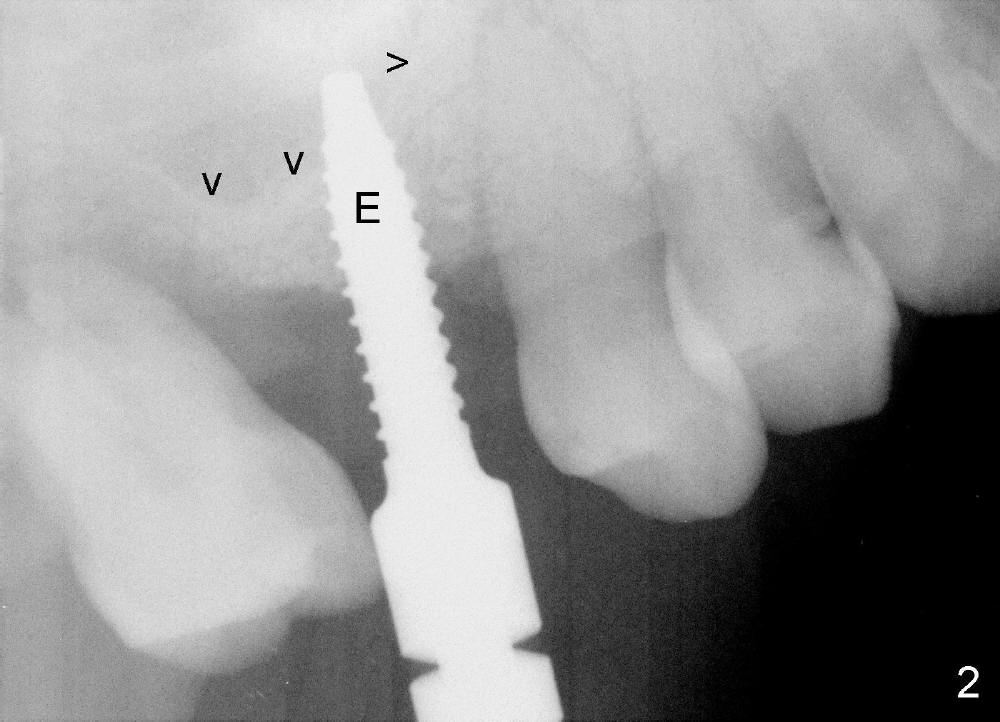

Bone expander kit is planned for for the case at the site of #3 with apparently normal buccolingual width (Fig.1). Bone density proves to be not low intraoperatively. First, when the 1.6 mm pilot drill is being used, the bone does not feel soft. Second, the first expander (2.6 mm, Fig.2 E) cannot be driven into the osteotomy (following the pilot drill) unless 2.5 mm reamer is used. Third, when larger expanders (until 3.8 mm) and 5x11 mm tap (Fig.3 T) are being used, the distobuccal plate starts to crack, although insertion torque of 5.3x8 mm implant is >50 Ncm (Fig.4). Using bone expanders is time consuming. In brief, when the buccolingual width is within normal limit and bone density is not low, traditional osteotomy should be adopted. It is better to use reamers to collect autogentous bone at the same time. The bone can be put back later into the osteotomy for sinus lift. Another drawback of this case is that the implant is not placed deep enough (Fig.5: 3 months postop). When a crown is cemented 1 year 4 months postop, the distal coronal portion of the implant is supragingival, although there is no infection.